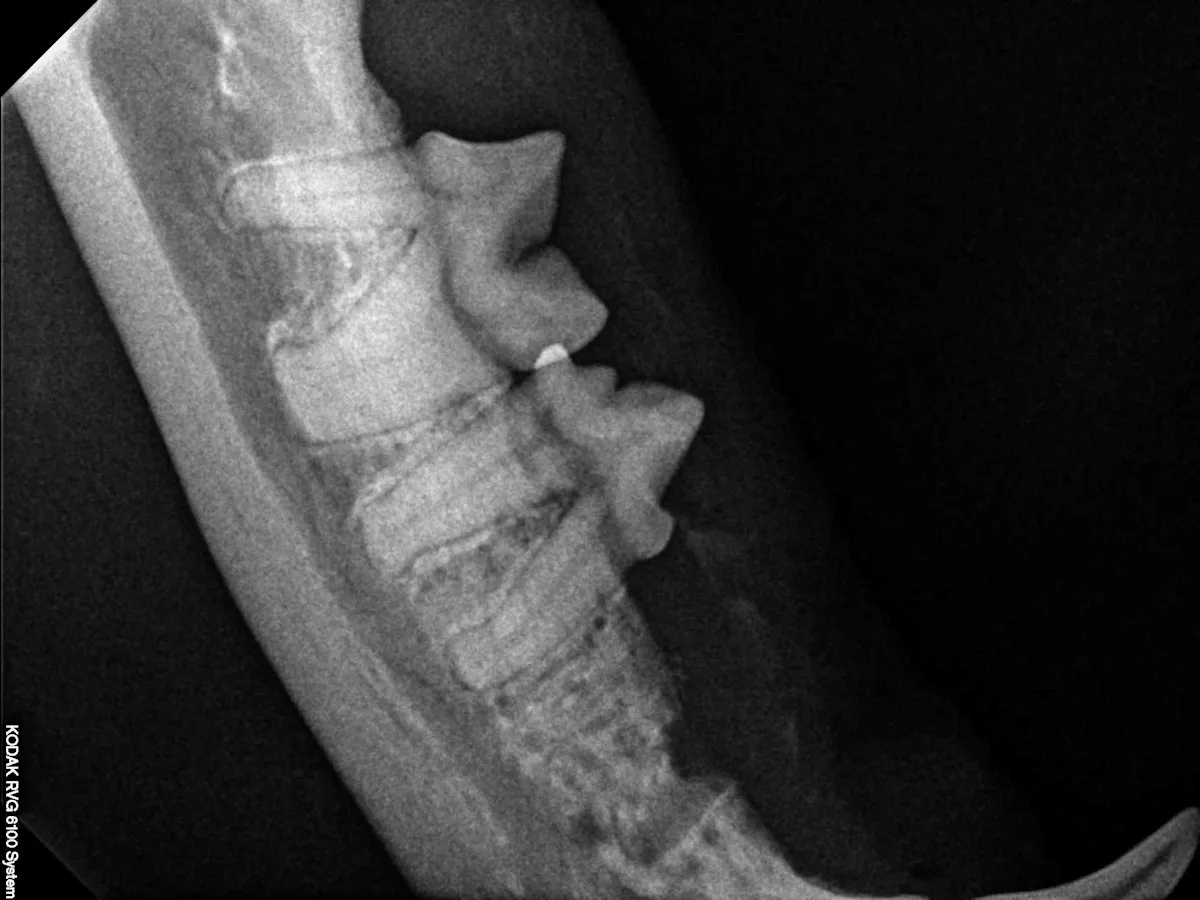

Step 11

An postoperative intraoral dental radiograph shows that the mesial root has been removed and the alveolar crestal bone over the distal root has been smoothed.